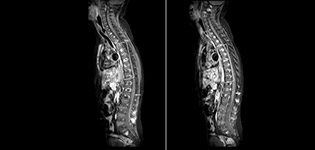

Routinely obtaining homogeneous fat suppression under virtually all conditions with mDIXON TSE

Philips mDIXON TSE is a two-point DIXON technique that separates water and fat signals, for time-efficient fat-free imaging, even in challenging neuro anatomy. “mDIXON TSE has been one of the most significant improvements in imaging sequences that we have utilized to date at PCH,” says Dr. Miller. “Its multi-parametric acquisition allows us to obtain fat suppressed images and equivalent non-fat suppressed T2 images all in the same sequence. In addition, prior methods of fat suppression could be artifactually corrupted by poor patient anatomy or poor operator application, but with mDIXON we now have a robust and reliable method of fat suppression.” Fat saturation is historically challenging at the ends of fields of view, especially in total spine imaging and in difficult patient anatomy such as the lower regions of the neck. “Due to the unique fat suppression capabilities of mDIXON, however, these challenges no long apply,” says Dr. Miller. “We routinely obtain homogeneous fat suppression under virtually all conditions. It has also led to some efficiencies by not having to repeat sequences because of that technical failure.”

mDIXON TSE makes a difference

“mDIXON TSE has increased our diagnostic confidence in ruling in or ruling out abnormalities in which fat suppression is critical to diagnosis, such as metastatic disease or osseous abnormalities.”

“mDIXON TSE is most useful in patients with lesions or abnormalities in the soft tissues such as the face and neck, and for patients with contrast enhancing abnormalities that are mostly visible with fat suppression,” says Dr. Miller. “All our spine imaging now routinely contains mDIXON water-only T2 images, and this allows us to identify pathology that may be obscured by non-fat suppressed imaging such as injuries of the bone. And it’s not necessary to obtain additional standard TSE T2 images because the in-phase mDIXON images are equivalent to standard TSE T2 images.”